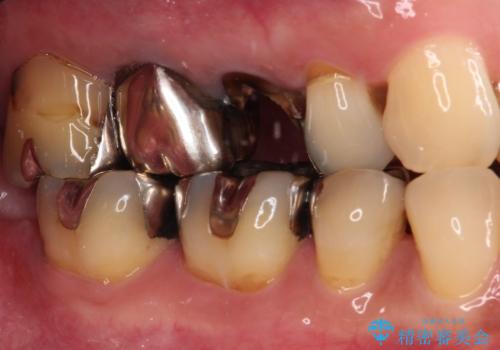

もげてしまった奥歯 オールセラミッククラウンでの補綴治療

- 食事中に歯がもげてしまったとのことで来院された患者様です。

レントゲン写真から、特に大きなむし歯などは認められませんでしたが、根管治療があまり十分に行われているとは言えない状態でした。

まずは仮歯を装着し、根管治療を行った上で土台を植立し、オールセラミッククラウンにて補綴治療を行うこととしました。

反対咬合で奥歯に負担のかかる咬み合わせのため、就寝時に強い力がかからないよう、マウスピースを装着していただくよう指示をしました。